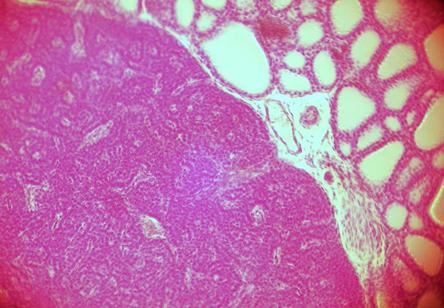

Клетки железы – паратироциты – полигональной формы, мелкие, ядра окрашиваются базофильно. Различают светлые и темные паратироциты. Темные – активно секретирующие, светлые – покоящиеся клетки. По периферии долек встречаются оксифильные паратироциты. Эти клетки по размеру крупнее, чем главные и их цитоплазма розовая. Количество оксифильных паратироцитов увеличивается с возрастом. Соединительная ткань стромы хорошо развита, однако дольки выражены плохо. В соединительной ткани трабекул много сосудов и адипоцитов.

При малом увеличении микроскопа:

а) найти и рассмотреть паратироциты. Паратироциты расположены группами. Границы клеток малоразличимы, хорошо видны только ядра.

б) найти капсулужелезы. Это слой оксифильно окрашенных волокон, расположенных по периферии органа.

в) найти междольковую соединительную ткань. В волокнах соединительной ткани расположены многочисленные сосуды и группы адипоцитов.

г) найти гемокапилляр

Фото. 3.3.1. Паращитовидная железа. Гем.-Эоз.

Малое увеличение. (Ув.10х7)